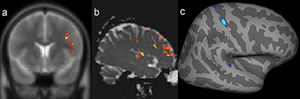

In one patient, there was concordance between the findings of the SBM evaluation, VBA of T2 maps, and the structural abnormality found on visual inspection of conventional MR images (Figure 3).

Example of a patient who switched to positive magnetic resonance imaging (MRI) status only after targeted visual evaluation guided by postprocessing (patient 19). A possible epileptogenic zone had not been regionalized in this patient with video electroencephalography. However, he exhibited abnormalities in the same region by two quantitative measures. a) Postprocessing of cortical thickness (quadrature decoder [QDEC]) showed temporo-insular thickening in the right hemisphere (blue image). b) Evaluation of T2 relaxometry maps with Statistic Parametric Mapping (SPM12) software also revealed a signal abnormality in the same location (yellow and red foci). c) Coronal T2 short tau inversion recovery (STIR) (inverted window) showing cortical thickening in the same region (black arrows).